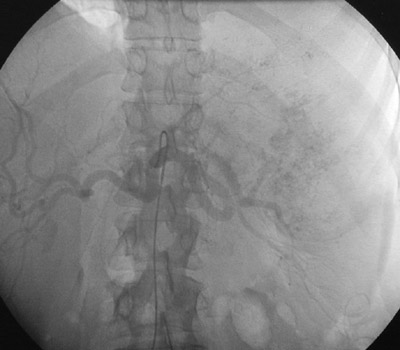

With injection of contrast into the celiac axis from the aorta, the angiographic views above and below demonstrate a vascularized mass involving the spleen. This is an angiosarcoma.